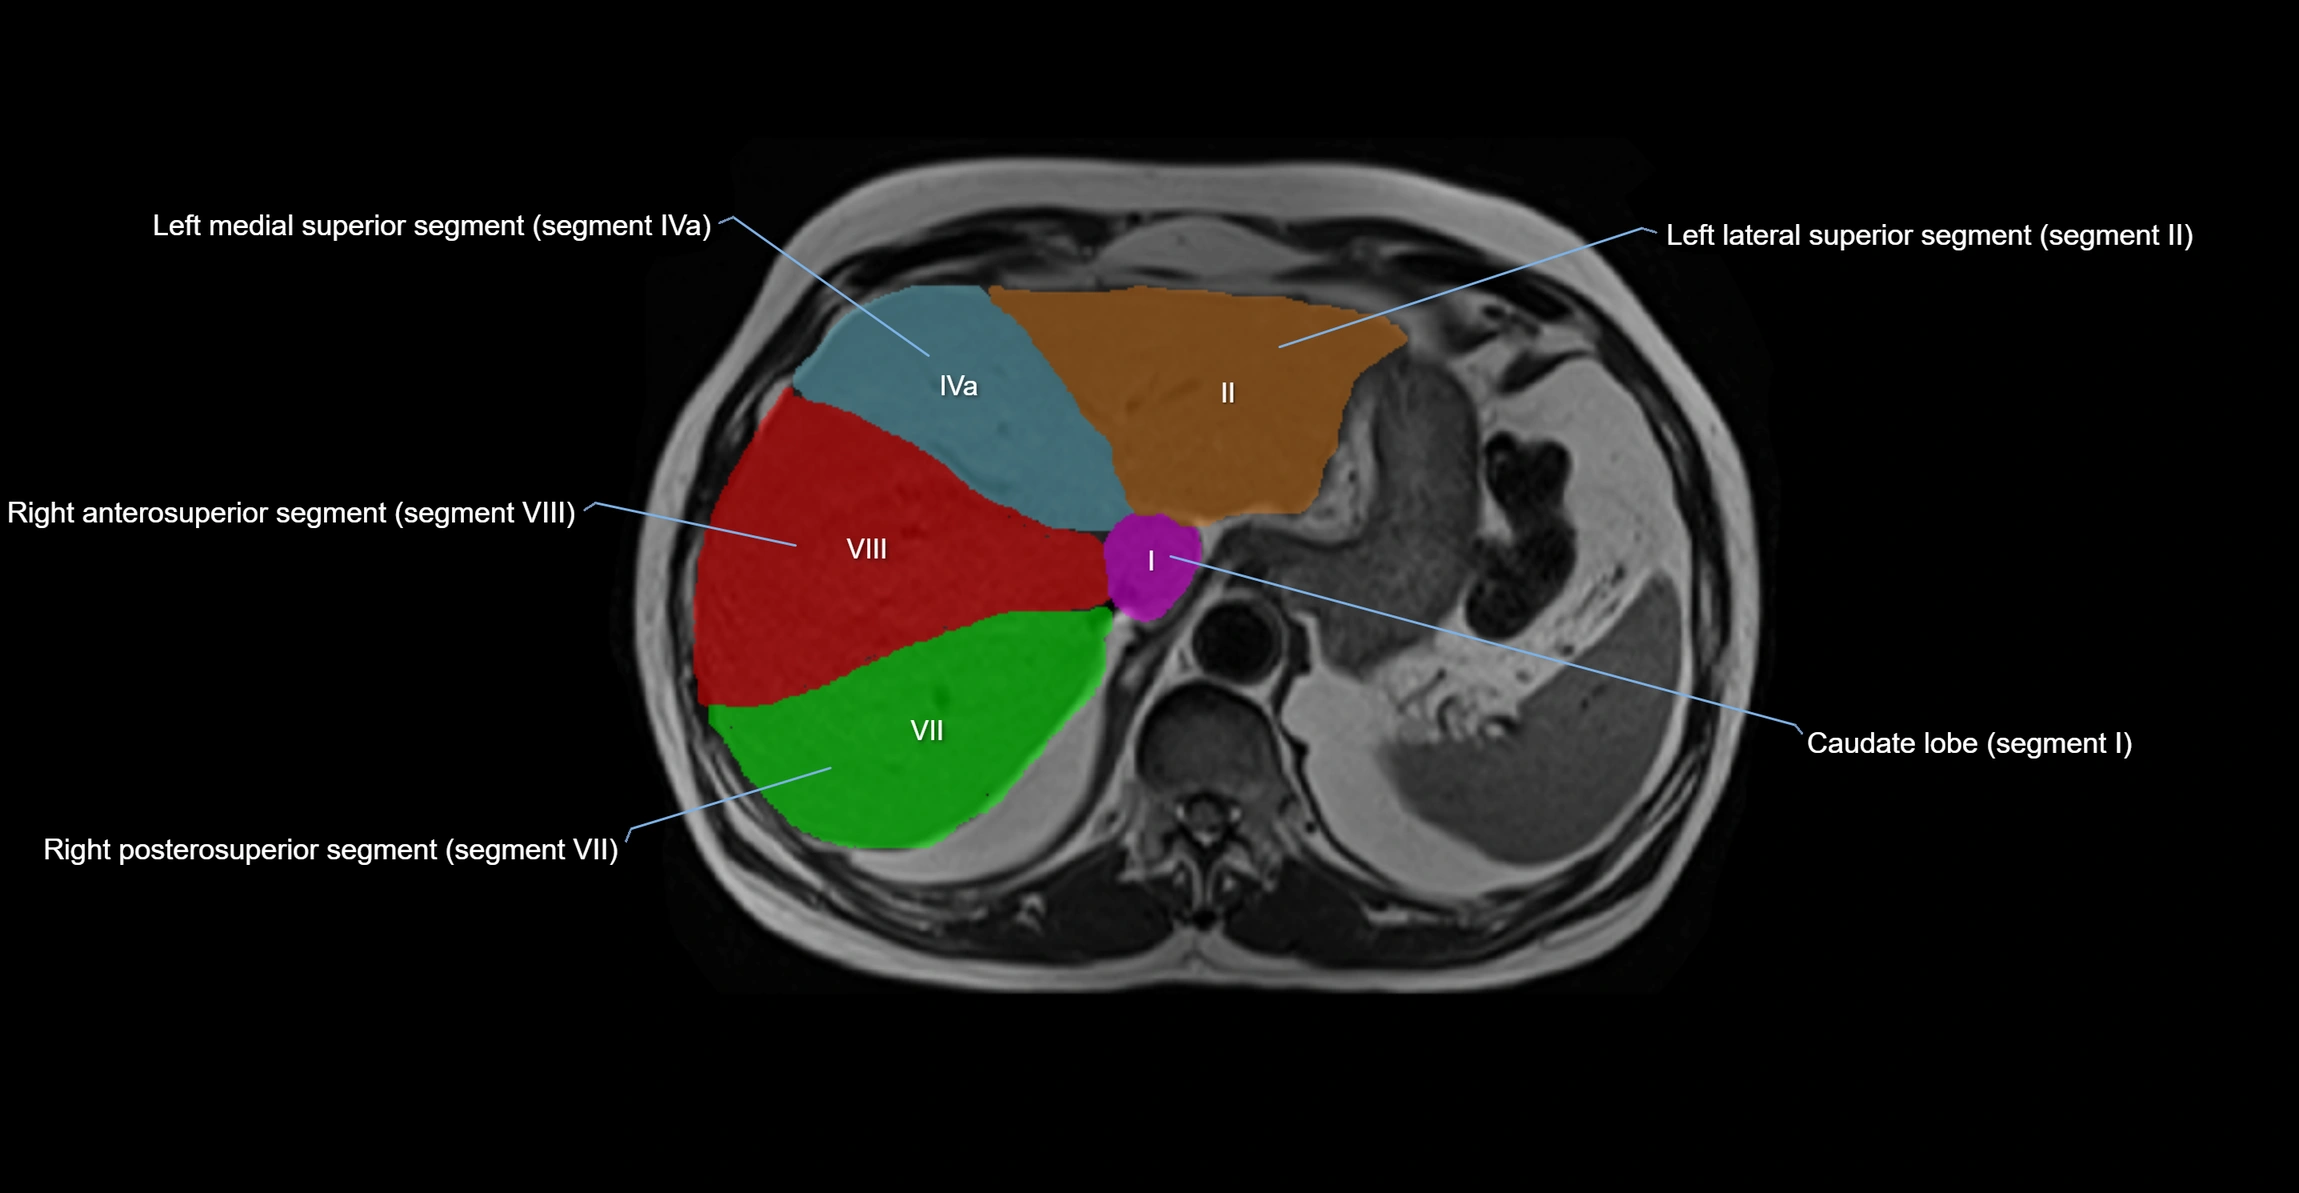

The caudate lobe of the liver is a distinct anatomical subdivision of the liver, designated as segment I in Couinaud’s classification. It lies on the posterior surface of the liver, between the fissure for the ligamentum venosum (left boundary) and the groove for the inferior vena cava (IVC) (right boundary). Superiorly, it is related to the posterior liver surface, and inferiorly it is separated from the left lobe by the porta hepatis.

The caudate lobe is unique because it receives dual portal venous and arterial inflow from both the right and left portal veins and hepatic arteries. It also has independent venous drainage directly into the IVC via multiple small hepatic veins, unlike other lobes that drain through the three main hepatic veins.

• Segment I (Couinaud classification)